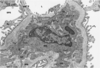

What is this?

glomerulus

E: endothelium

F: fenestration

C: capillary

BM: basement membrane

P2: secondary podocyte process

FS: filtration slit